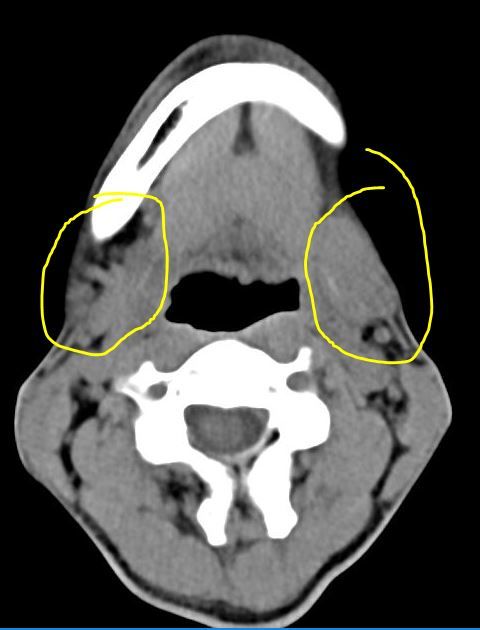

8월부터 밥먹을때마다 턱밑 침샘이 붓길래 이비인후과 가서 ct 검사해보니 타석증이 있다고합니다

그리고 침샘위축이 됐고 침샘염증이 있다고합니다

• 1번 째 사진

• 2번 째 사진